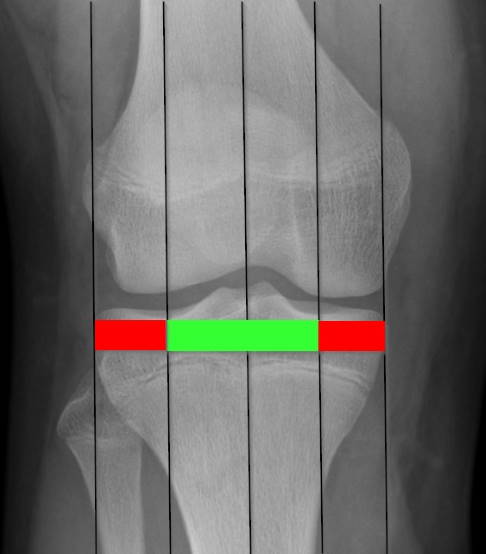

Zur Einschätzung der Beinachsenfehlstellung wird die Ganzbein-Röntgenaufnahme des Kniegelenks von vorne in 4 Quadranten eingeteilt. Verläuft die Mikulicz-Linie und somit die mechanische Beinachse innerhalb der beiden mittleren Quadranten, liegt eine normale bzw. geringgradig abweichende Beinachse vor, die nicht operativ korrigiert werden muss. Verläuft die Beinachse außerhalb der inneren Quadranten, liegt eine pathologische (krankhafte) Beinachse vor.

Um die mechanische Achsdeviation (MAD), also das genaue Ausmaß der Abweichung von der Mitte des Kniegelenks abzuschätzen, ermittelt der Kniespezialist die Mikulicz-Linie. Diese bestimmt er anhand der Röntgen-Ganzbeinaufnahme. Sie führt vom Zentrum des Hüftkopfes bis zur Mitte des oberen Sprunggelenks. Verläuft die Mikulicz-Linie nicht mittig durch das Kniegelenk, sondern durch die Innenseite, handelt es sich um eine Varusfehlstellung (O-Bein). Verläuft sie durch die Außenseite des Kniegelenks, liegt eine Valgusfehlstellung (X-Bein) vor. Zusätzlich wird der exakte Winkel der Achsabweichung ausgemessen.

Die Mikulicz-Linie ist eine gedachte Linie vom Zentrum des Hüftkopfes bis zur Mitte des oberen Sprunggelenks. Orthopäden nutzen die Mikulicz-Linie zur Bestimmung der mechanischen Tragachse. Bei einer geraden Beinachse verläuft die Mikulicz-Linie durch die Mitte des Kniegelenks. Verläuft sie durch die Innenseite des Kniegelenks, handelt es sich um eine Varusfehlstellung (O-Bein). Bei einer Valgusfehlstellung (X-Bein) verläuft sie durch die Außenseite des Kniegelenks. Im Gegensatz zur anatomischen Achse, die durch die Knochen gebildet wird, bildet die Mikulicz-Linie die mechanische Achse. Besonders am Oberschenkel ist der Unterschied zwischen mechanischer und anatomischer Achse sehr groß.